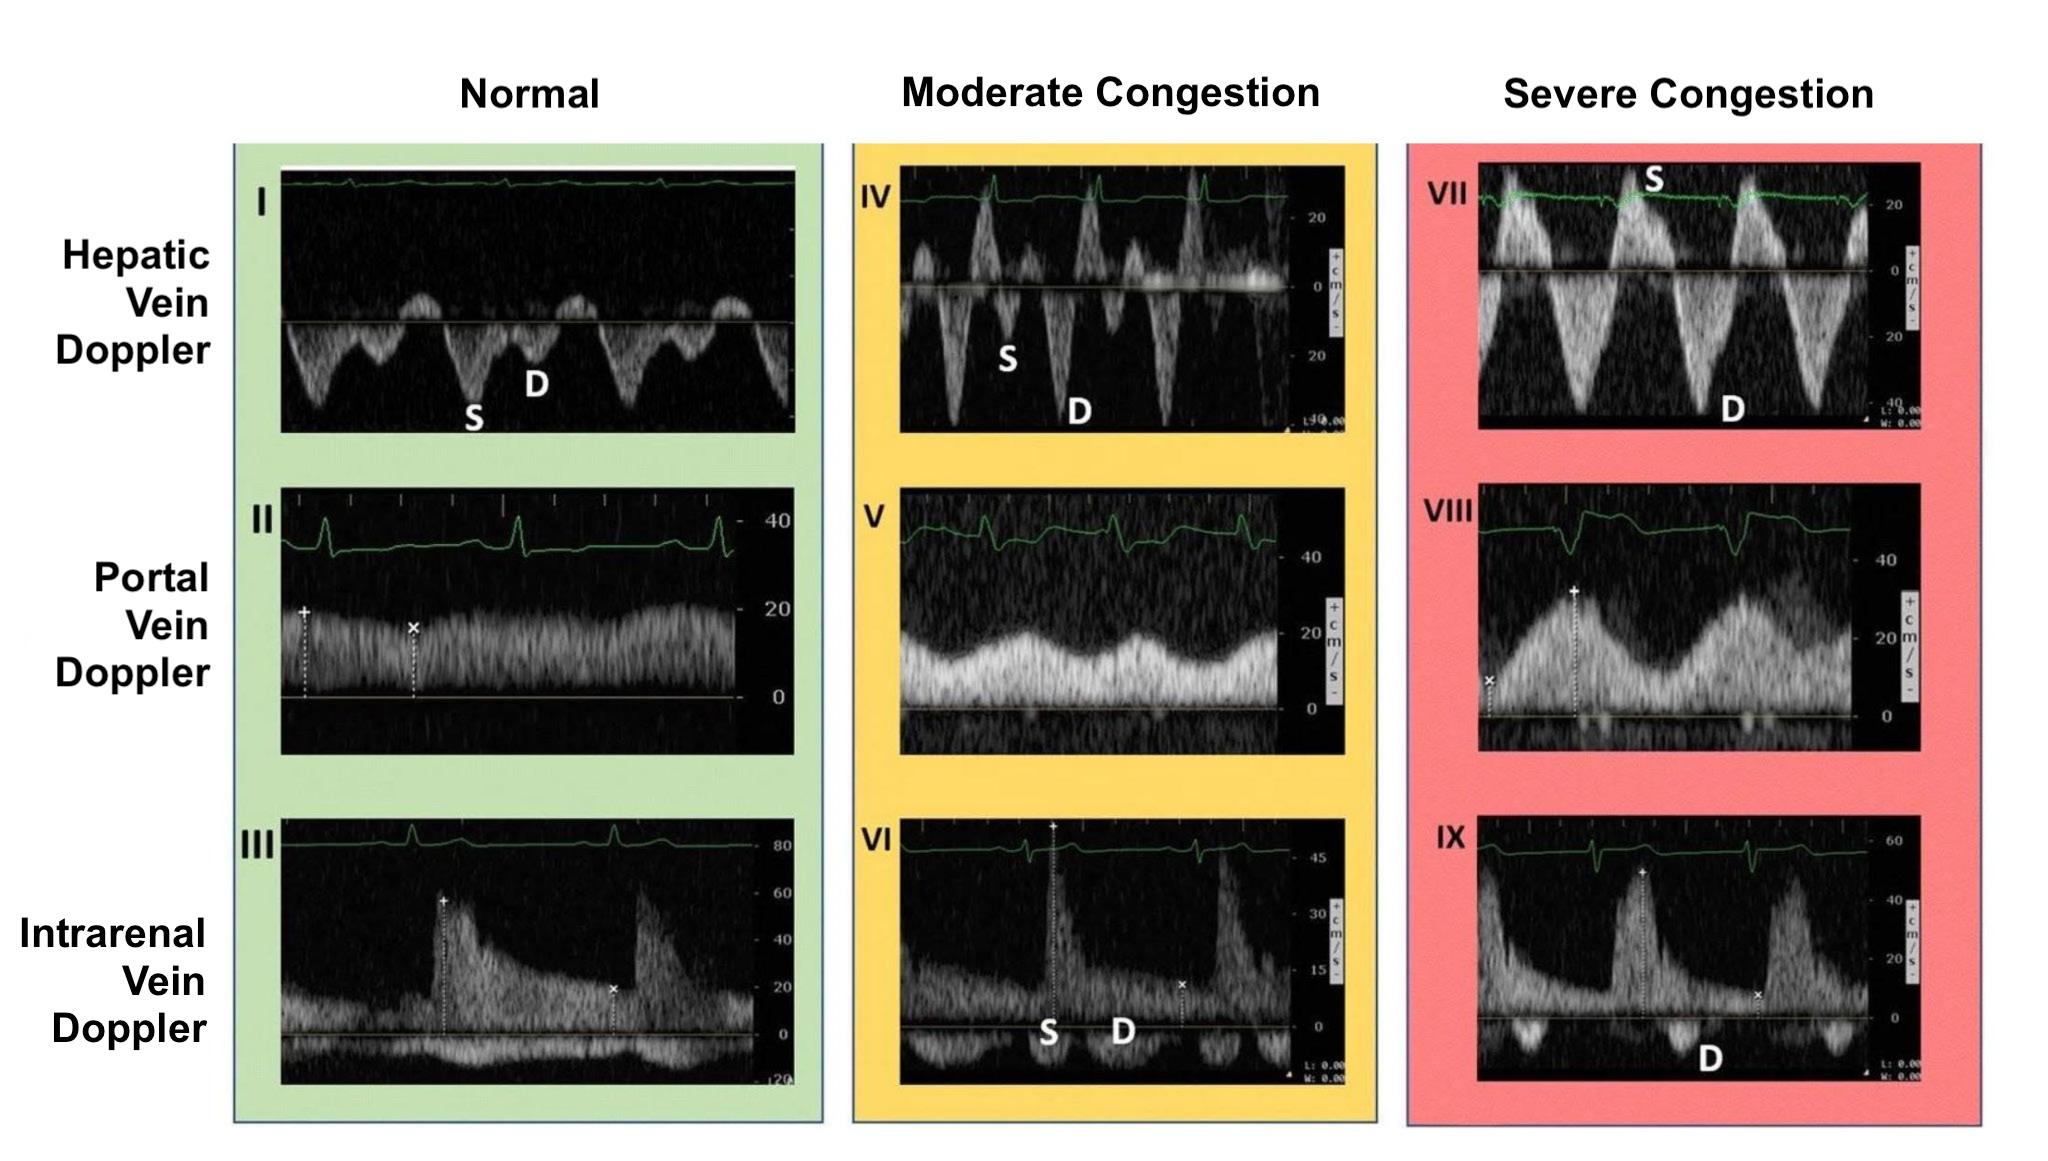

Venous Congestion at the Bedside Using the VExUS Protocol

That Matter: The Power Of Bedside Ultrasound